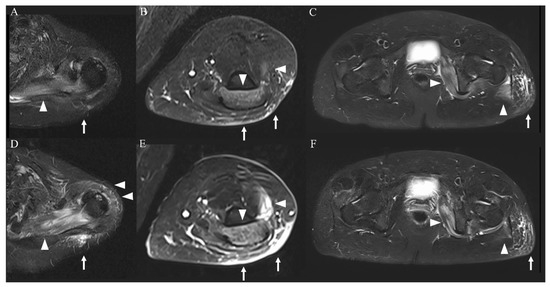

- Lamminen, A.E.; Hekali, P.E.; Tiula, E.; Suramo, I.; Korhola, O.A. Acute rhabdomyolysis: Evaluation with magnetic resonance imaging compared with computed tomography and ultrasonography. Br. J. Radiol. 1989, 62, 326–330. [Google Scholar] [CrossRef]

- Shintani, S.; Shiigai, T. Repeat MRI in acute rhabdomyolysis: Correlation with clinicopathological findings. J. Comput. Assist. Tomogr. 1993, 17, 786–791. [Google Scholar] [CrossRef] [PubMed]

- Lu, C.H.; Tsang, Y.M.; Yu, C.W.; Wu, M.Z.; Hsu, C.Y.; Shih, T.T.F. Rhabdomyolysis: Magnetic Resonance Imaging and Computed Tomography Findings. J. Comput. Assist. Tomogr. 2007, 31, 368–374. [Google Scholar] [CrossRef]